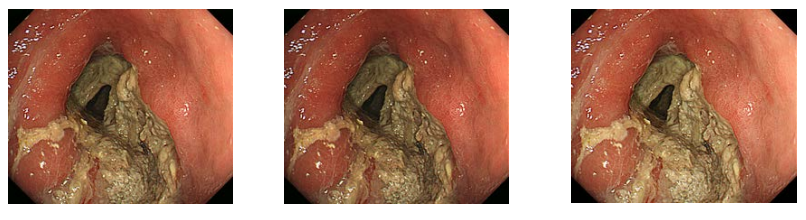

Poniżej zestawiono oceniane obrazy dla porównania:

2) Skuteczność diagnozy opartej na kolorowych badaniach z krzywą Gamma 2.2

Rys. 10 pokazuje, że dla 31,5 z 86 kolorowych obrazów (ok. 37%) tryb Hybrid Gamma PXL stosujący „mieszaną” krzywą Gamma 2.2 został oceniony lepiej niż tryb krzywej gamma GSDF, a wśród ocenionych w ten sposób badań znalazły się wyłącznie obrazy ES lub RI, bez obrazów US. Nie zdarzyło się, by tryb DICOM GSDF został oceniony lepiej niż tryb Hybrid Gamma stosujący „mieszaną” krzywą Gamma 2.2.